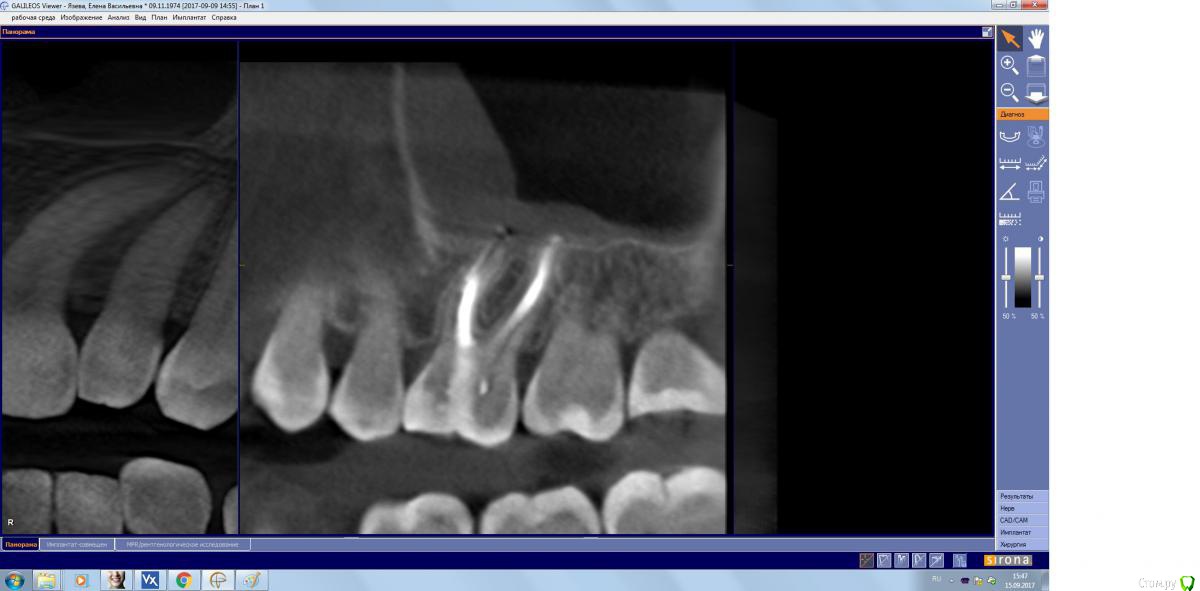

kamranchick Опубликовано 15 сентября, 2017 Поделиться Опубликовано 15 сентября, 2017 Господа, терапевт наш пролечил зуб, и болит пазуха уже месяц... сам зуб не болит, какой план действий? Ссылка на комментарий

kamranchick Опубликовано 15 сентября, 2017 Автор Поделиться Опубликовано 15 сентября, 2017 (изменено) Лор говорит хронический гайморит в стадии обострения, но провоцирует зуб, короче все как всегда... Изменено 15 сентября, 2017 пользователем kamranchick Ссылка на комментарий

kamranchick Опубликовано 15 сентября, 2017 Автор Поделиться Опубликовано 15 сентября, 2017 хотя бы узнать, это по нашей части, вернее мы виноваты или это со стороны лор что то, куда пациента определять... или опять в зуб лезть Ссылка на комментарий

parallax Опубликовано 16 сентября, 2017 Поделиться Опубликовано 16 сентября, 2017 Это пристеночно-гиперпластическая форма гайморита, застарелая хронь, которая появилась не вчера. Возможно, обострение спровоцировали паффы (куда ж без них). Я думаю, стоматологи тут не при чём. Хотя ЛОРики всегда обвиняют нас (скоро вменят убийство Кеннеди). В каналы лезть больше не надо, отправляйте в ЛОР отделение, лечение этого гайморита хирургическое. 1 Ссылка на комментарий